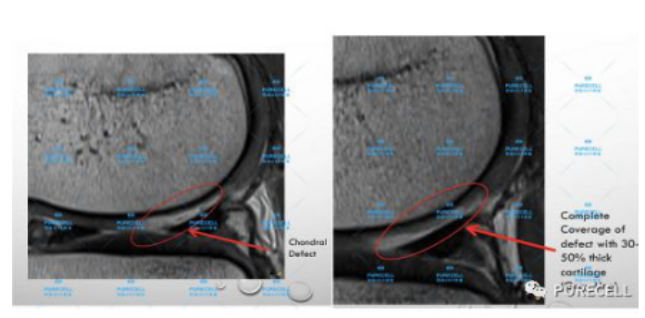

PURECELL首席科學家以及運動醫療專家已經驗證了UCF對膝關節修復的有效性,下圖是UCF軟骨及半月板修復前後影像對比。

1573812945fAlVkMoJ.png

1573812957iCHlU6yh.png

UCF膝關節修復的主要原理是通過UCF成分,改善膝關節內環境,有效激活幹細胞靶向修復膝關節組織,修復韌帶損傷、半月板損傷,修復軟骨及髕骨等組織,能有效減少軟骨受損、骨刺等所帶來的疼痛,並且有效避免了軟骨半月板等膝關節組織的持續磨損和惡化,從根源上改善膝關節疼痛等問題給生活帶來的困擾。